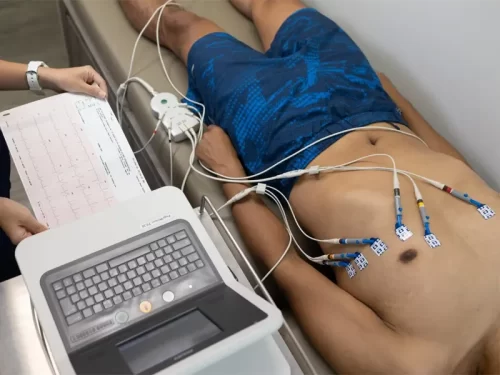

- نوار قلب

- تست ورزش